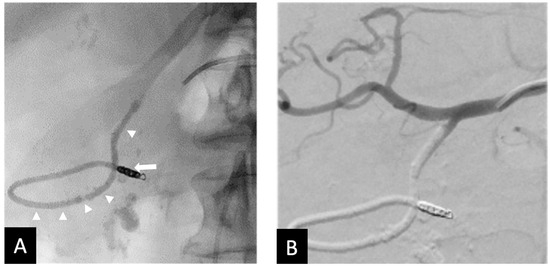

In the two clinical failures, inadequate embolization was performed. Specifically, the GDA was not occluded proximally to its origin in one patient, leaving the SPDA patent, which led to rebleeding which was subsequently embolized with coils (Figure 5). The second patient required a second embolization to address collateral flow from the pancreatico duodenal arcade (Figure 6). This was thought to be due to inadequate distal placement of the backstop coil into the proximal RGEA. It is also worth noting that in one patient small fragments of Ta-OCE entered the hepatic artery due to rapid microcatheter movement with no clinical adverse events observed (Figure 6B). Of note, no ischemic bowel was noted. At 6 months, 9 of 10 patients did not require additional embolization, indicating durable clinical outcomes. One patient died due to complications from an invasive tumor, unrelated to the embolization procedure.

Figure 5. Rebleed example of unembolized SDA—(A) Post-embolization radiograph showing 3 mm coils in the proximal RGEA and inferior pancreaticoduodenal artery (arrows). Continuous column of Ta-OCE extending from the coil pack in the proximal RGEA to the proximal GDA (arrow head). An endoluminal clip placed during endoscopy is also demonstrated (*). (B) DSA with contrast injection from the CHA shows patent SDA (arrow) and proximal GDA (arrowhead). This patient required a second embolization to address the SDA. Image obtained from patient’s chart. Source: NK.